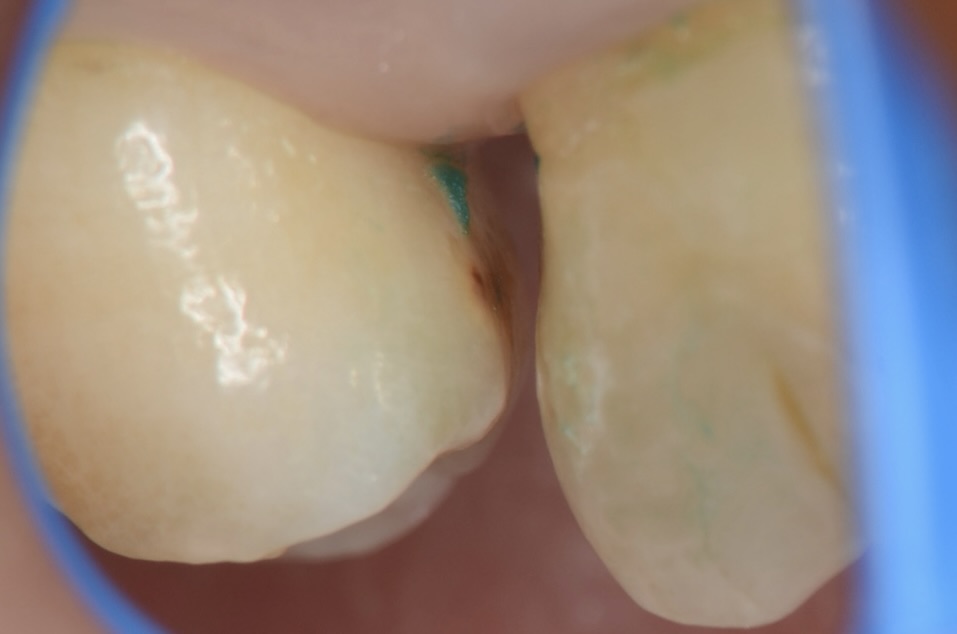

歯間離開確認

ゴムを外すと隙間ができています。そこから覗くと7番の近心に虫歯が見えます。 -

6番遠心の虫歯

6番の遠心にも虫歯が見えます。 -